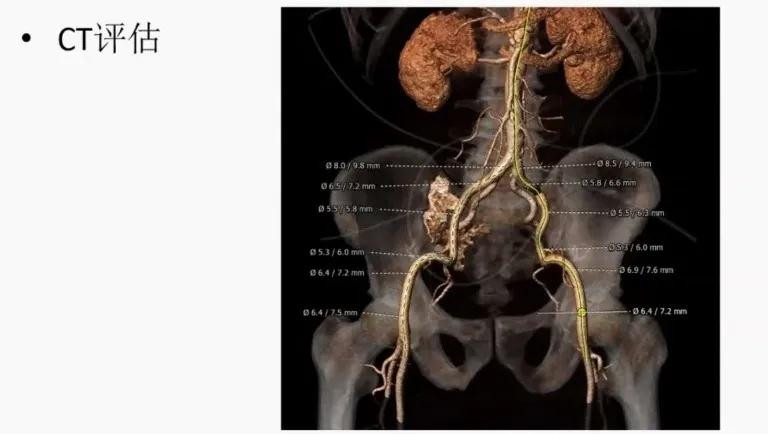

TAVR CT评估:主动脉瓣二瓣化畸形,TYPE 1型,左右窦融合;瓣叶中重度钙化;升主动脉瘤样扩张;冠状动脉未见明显狭窄病变,左右冠开口较高,无冠脉阻塞风险;双侧股动脉迂曲,直径尚可。手术选择右侧股动脉20F鞘管主入路,根据瓣环和瓣上结构,预估选择26mm或29mm Venus A-Valve(杭州启明)。术中23mm Numed球囊预扩,通过balloon sizing确定瓣膜直径。

CT主动脉根部评估

CT冠脉开口评估

CT外周路径评估